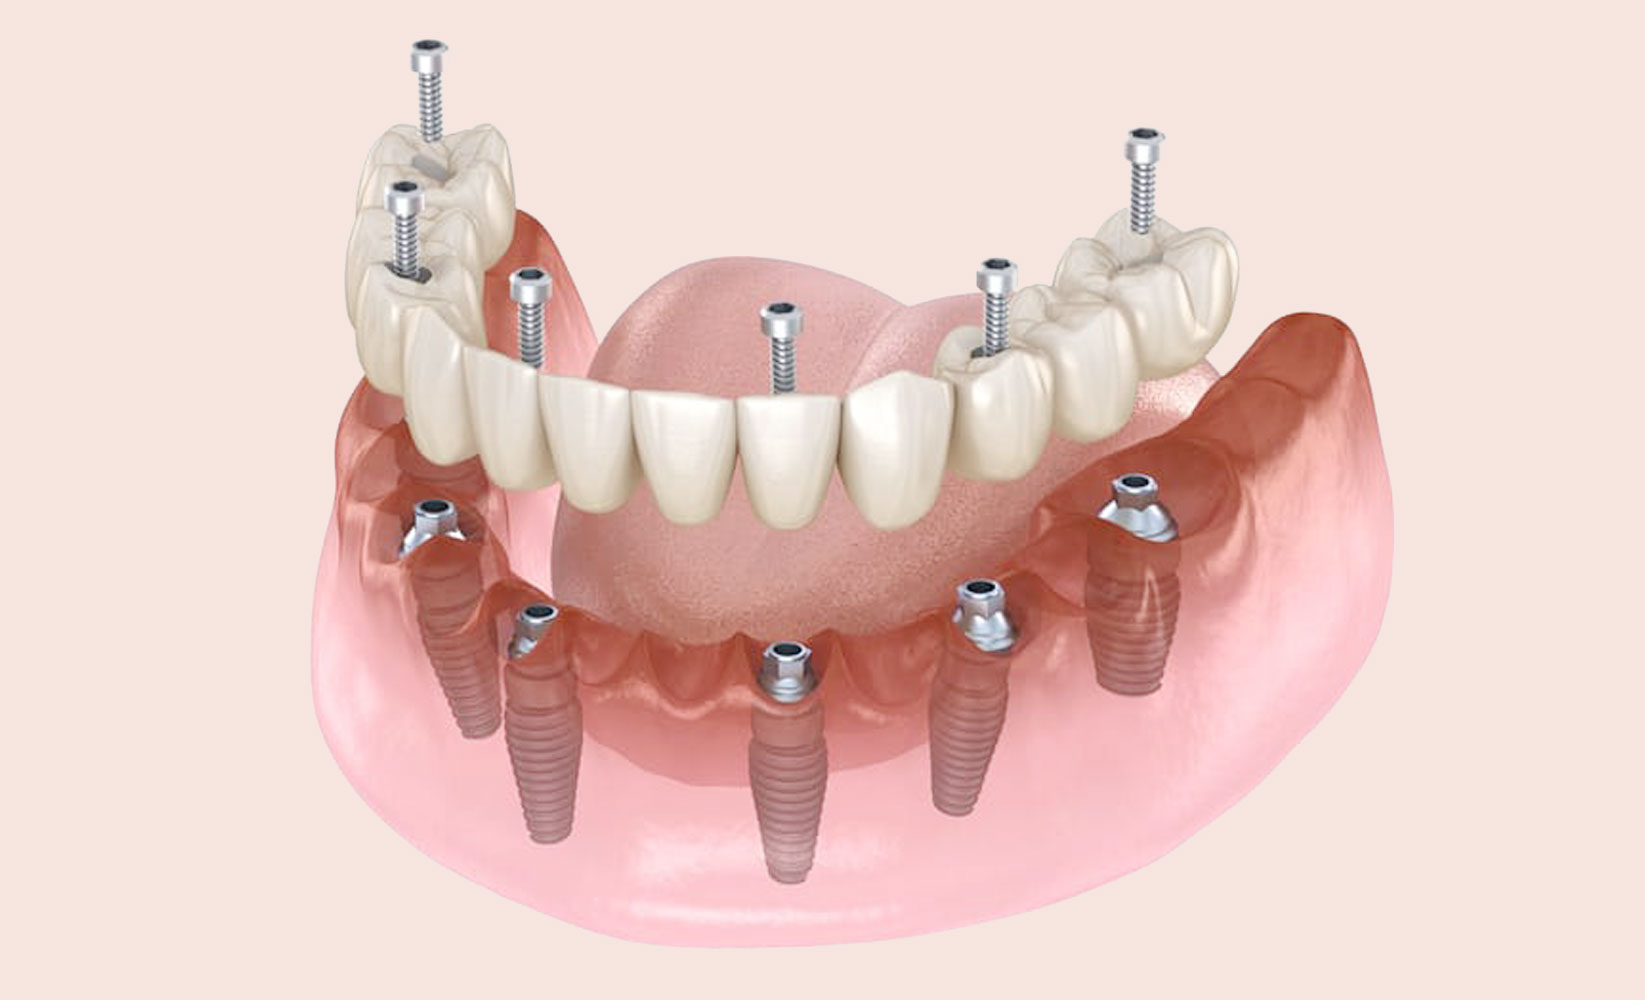

A Dental Implant is a titanium screw which is surgically inserted into the jawbone beneath the gum line to work as a tooth root. Post insertion, an implantologist will attach a crown on top of the Implant to ensure the appearance of a natural tooth.

Among the various types available, three prominent options include single implants, All-on-4, and All-on-6 dental implants.

All-on-4 Dental Implants

This method is for those missing most or all of their teeth in one or both dental arches. All-on-4 involves the placement of four implants in positions within the jawbone to support an entire arch prosthesis. This technique maximizes existing bone support, reducing the need for bone grafting, and allows for immediate placement of a temporary prosthetic set of teeth on the same day as the implant surgery.

All-on-6 Dental Implants

Similar to the All-on-4 approach, the All-on-6 technique provides a secure and stable solution for extensive tooth loss. This method strategically positions six implants in the jawbone to support a fixed prosthesis. The additional implants offer increased stability and strength, which is particularly beneficial for individuals who require additional support due to extensive bone loss or a more comprehensive restoration.